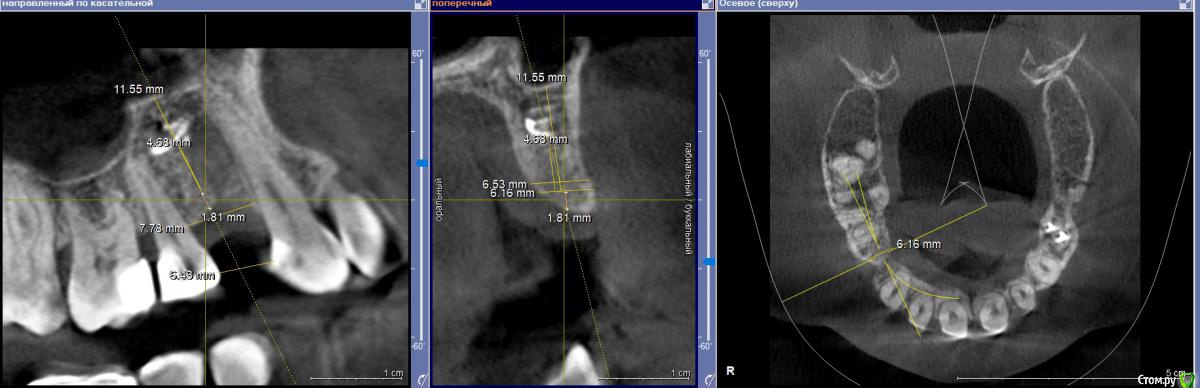

zumanok Опубликовано 19 января, 2020 Поделиться Опубликовано 19 января, 2020 Здравствуйте доктора. На этой неделе появилось два клинических случая. В обоих случая проекция будущих имплантатов располагается в области пломбировочного материала. На форуме есть подобные темы, но в данном случае прямой контакт с материалом. Стоит ли пытаться полностью убирать материал?Делать отдельный доступ? Как вариант сначала попробовать просверлиться на глубину материала и твердосплавным шариком 1000 об с максим. охлаждением поработать по стенкам ложа. Дополнительно делать РГ контроль.Как бы вы поступили в данных случаях? Ссылка на комментарий

dok1 Опубликовано 20 января, 2020 Поделиться Опубликовано 20 января, 2020 От объема, капсулы. Чуйки , в конце концов . Можно поиграть положением импланта и в первом и во втором случаях. Обойти дегко и там и там 2 Ссылка на комментарий

masterdent Опубликовано 20 января, 2020 Поделиться Опубликовано 20 января, 2020 можно обойти, но лучше рентгенкотроль по готовности шахты, тогда ясно будет, ушел материал на фрезе или нет Ссылка на комментарий

zumanok Опубликовано 21 января, 2020 Автор Поделиться Опубликовано 21 января, 2020 От объема, капсулы. Чуйки , в конце концов . Можно поиграть положением импланта и в первом и во втором случаях. Обойти легко и там и там Во втором случае тоже думаю что можно обойти, но вот в первом случае по мне только через материал.Фрезой можно выбрать. 2-х милиметровой. Обычно там рыхлее кость.Спасибо попробую, а как на счет твердосплавного бора? Поидее им проще работать будет и лишнего особо не уберешь. Ссылка на комментарий